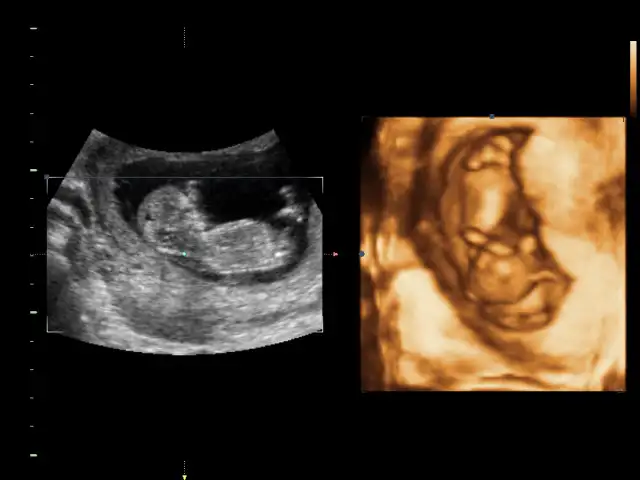

Bacakları açık aslında hiç çıkıntı yok gibiBu bebek durusu degisik geldi goremedim bisey canim

Kıza benziyor bence.Fikri olan var mı acabaEki Görüntüle 1530236

Kiz bence cikinti yokFikri olan var mı acabaEki Görüntüle 1530236

Canım kıza daha çok benzettim ben :)